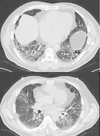

Consolidação com cavitação em lobo superior direito

Adenocarcinoma

Consolidação em lobo superior direito com áreas de cavitação

Padrão de micronódulos centrolobulares com árvore em brotamento

TB pós primária.